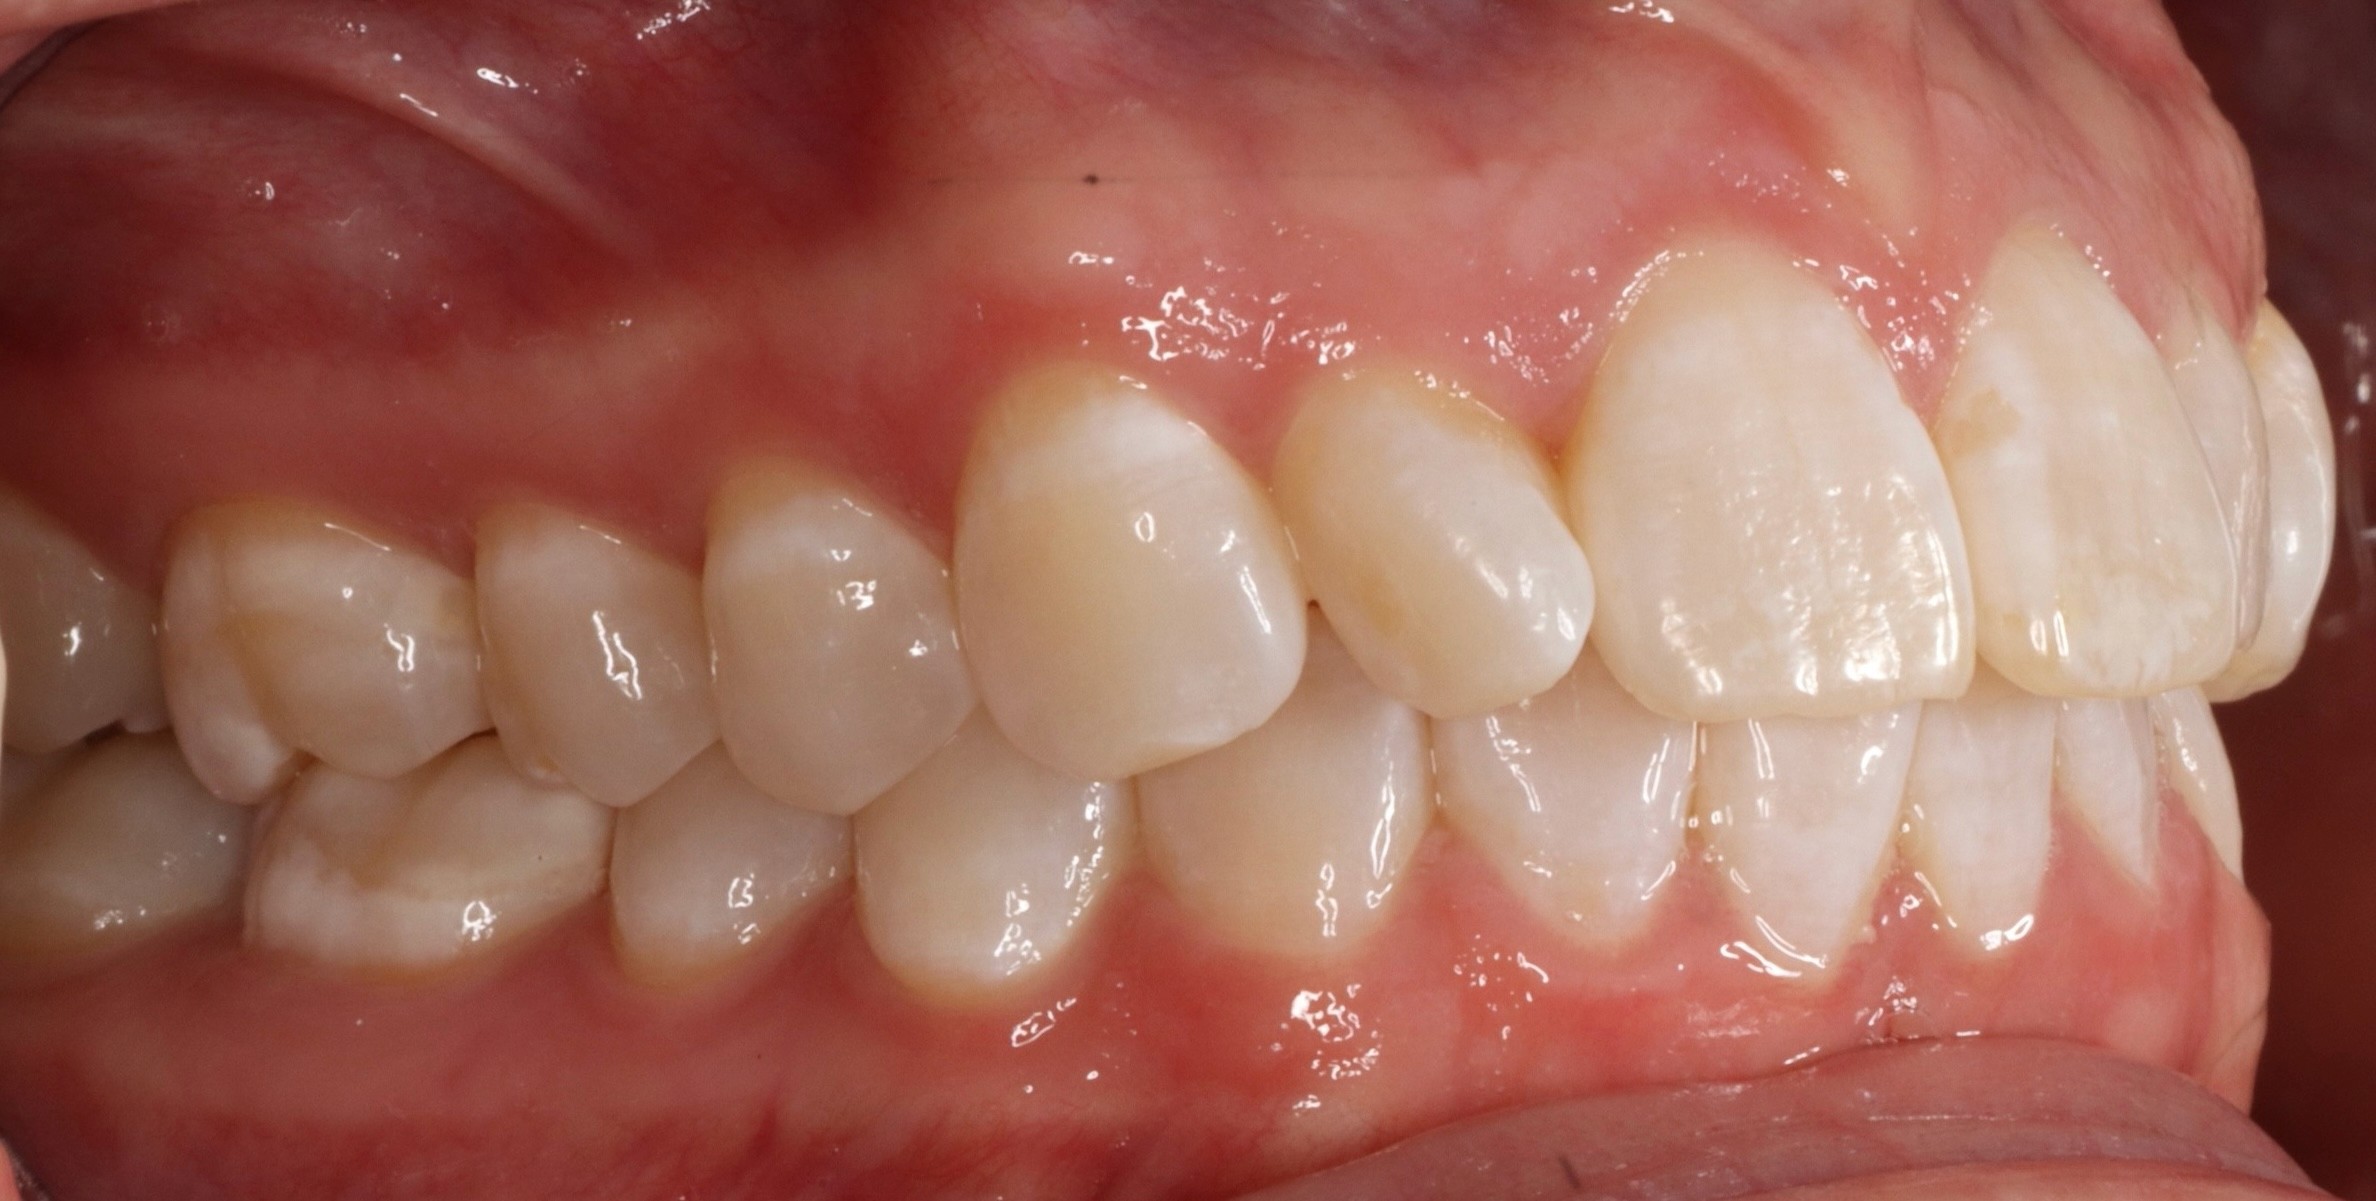

Diagnosis: Deep bite, lower anterior crowding, rotated upper lateral, arch misalignment, wear on teeth from grinding

Adjuncts: Attachments, IPR

Initial treatment

INTRAORAL